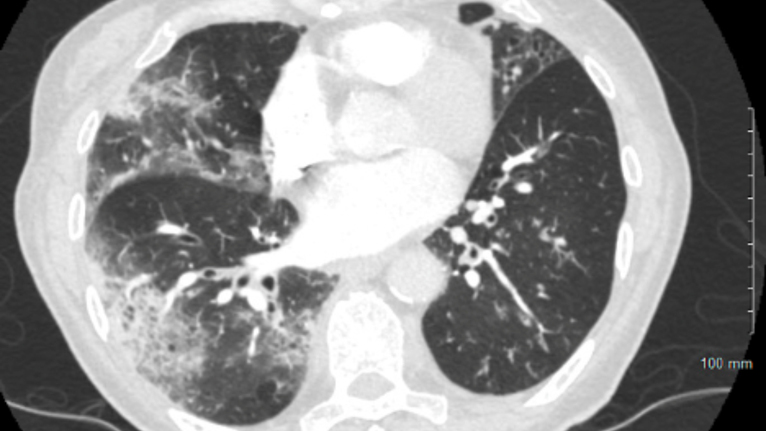

• CT Scan: A computed tomography (CT) scan provides detailed images of the lungs and can help identify emphysema or other lung abnormalities.